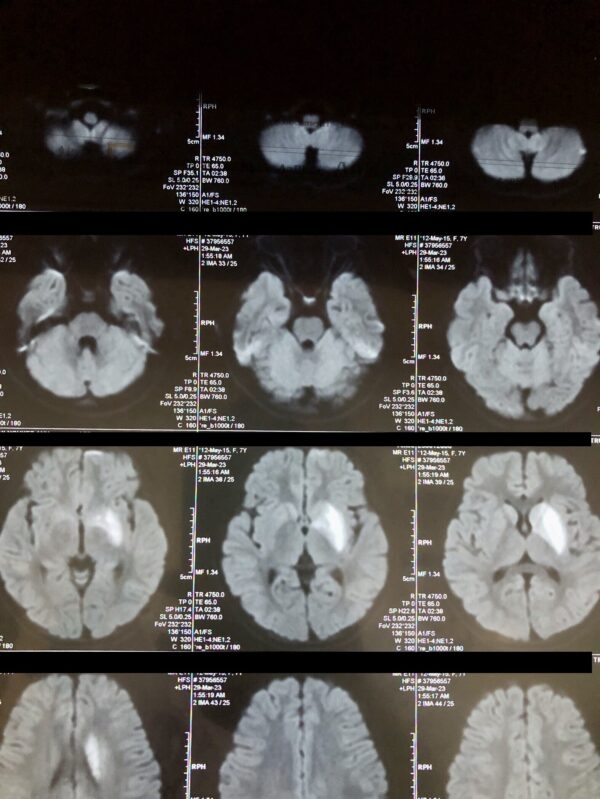

Ngay lập tức, cháu được sơ cứu ban đầu tại Trung tâm Y tế huyện trước khi chuyển thẳng xuống Bệnh viện Nhi Trung Ương và cháu được chẩn đoán: Nhồi máu não nhân bèo trái không rõ nguyên nhân – Liệt dây thần kinh số 7 ngoại biên phải.

| Ảnh: BVĐK tỉnh Phú Thọ |